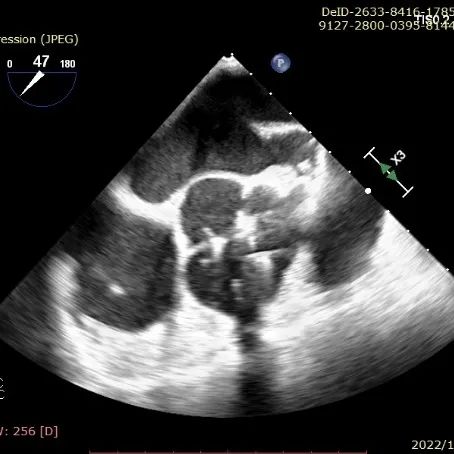

TEE提示定位件准确入窦

TEE提示瓣膜形态、位置良好